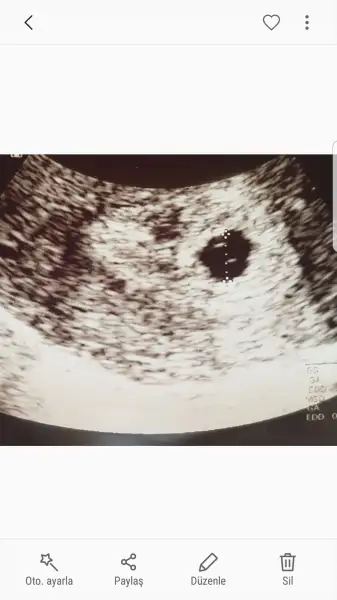

kızlar merhaba. ben bugün karından muayene oldum doktorun ultrasonuna göre 6+0 günlük çıktı kesem. ama bebeği henüz göremedi doktor. bu normal mi??

masallah canım. ben 5+3 te keseyi gördüm. ama benim ki erken döllenme. yani normalde 6+0 gibiyken gördüm diye düsünebilirsin. fakat doktorum alttan muayene ile bakmisti. kesenin icinde bir de yolk sac olması gerekiyormuş. onu da gördügü zaman doktor bu gebelik boş gebelik degil yorumunu yapabiliyor. yolk kesesi de var miydı içinde? bak 5+3 usg mi paylasıyorum. kesenin icinde 2 tane nokta goreceksin, o yolk kesesinin iki kenariymış.kızlar merhaba. ben bugün karından muayene oldum doktorun ultrasonuna göre 6+0 günlük çıktı kesem. ama bebeği henüz göremedi doktor. bu normal mi??